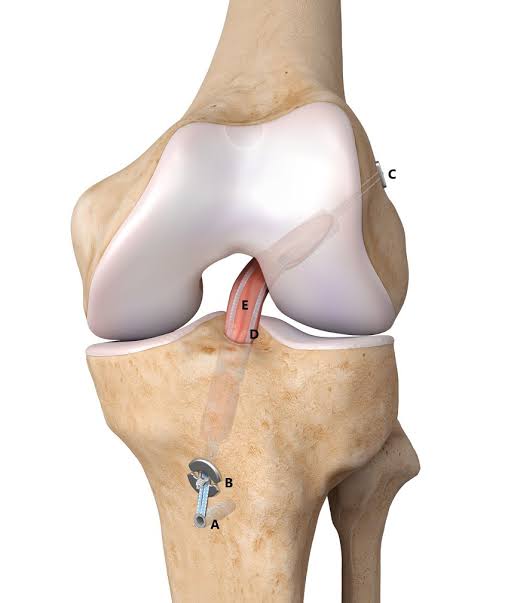

Anterior Cruciate Ligament (ACL)

The Anterior Cruciate Ligament (ACL) is one of the key ligaments that help stabilize the knee joint. It connects the femur (thigh bone) to the tibia (shin bone). The ACL runs diagonally in the middle of the knee, preventing the tibia from sliding out in front of the femur, and providing rotational stability to the knee.